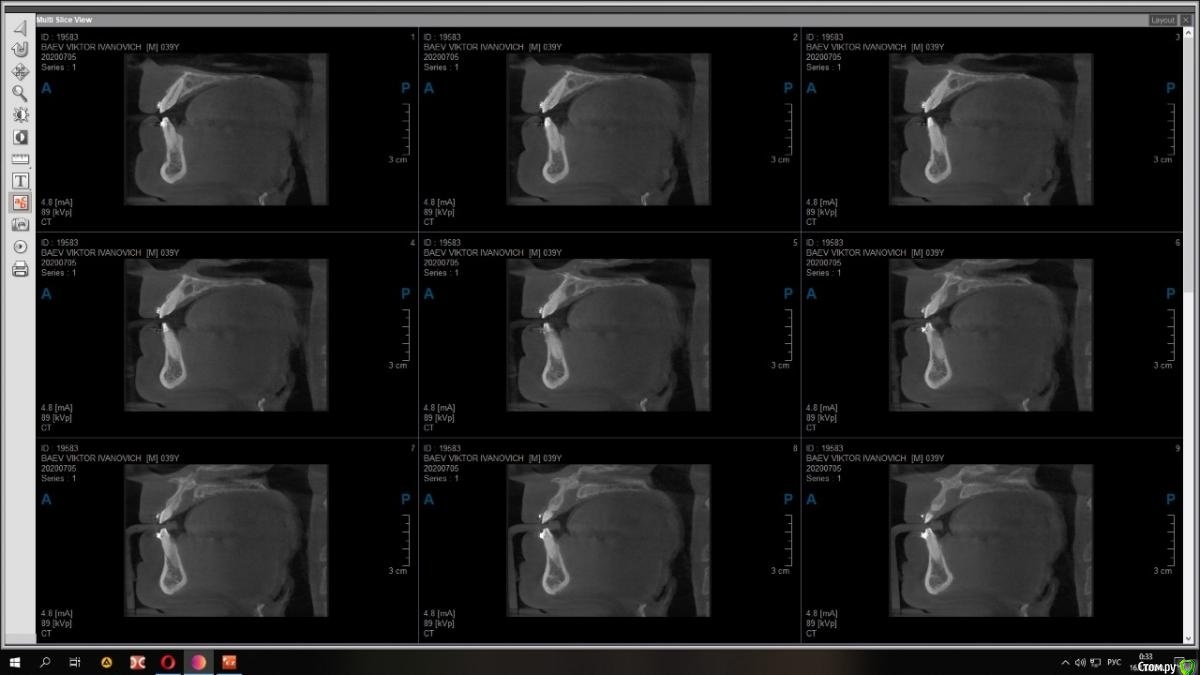

Raystom Опубликовано 15 декабря, 2020 Поделиться Опубликовано 15 декабря, 2020 Случайно на КТ перед имплантацией 36 обнаружили образование. Похоже на кисту резцового канала. Срезы снимка прилагаются.Варианты решения:1. Стационар и ЛОР, т.к. судя по снимку она, на мой взгляд, состоит из 2х частей и есть очень большая вероятность прорастания в носовой ход2. Убирать самостоятельно, но тут возникает очень много вопросов. С нёба доступ самый простой, но потом непонятно как закрыть костный дефект так, чтобы была возможность восстановления кости. При вестибулярном доступе предварительно придется делать эндо 111 с последующей резекцией, но, непонятно, удастся ли его вообще сохранить. Ещё момент, если убрать только обширную часть (нижний компонент), положить резорбируемую мембрану на дно, а аугментат через 2 месяца, дабы не пророс. При этом верхний компонент убрать с помощью ЛОР-эндоскопии.И организационный вопрос, как будет лучше, как и планировалось провести имплантацию 36, дать человеку отдохнуть на новогодних праздниках, а после уже лечение по поводу кисты Ссылка на комментарий

Raystom Опубликовано 18 декабря, 2020 Автор Поделиться Опубликовано 18 декабря, 2020 Срезы из других проекций Ссылка на комментарий

Raystom Опубликовано 21 декабря, 2020 Автор Поделиться Опубликовано 21 декабря, 2020 Киста то малюсенькая. Вскрыть и почистить. Нёбно конечно же. Можно положить мембрану, в полость ничего не класть. В нос я бы вообще пока не лез. меня смущает 3 момента, первый это то, что она прилетит рядом с апикальной частью 11, второй это то, что мне показалось она состоит из 2х частей и третье, это то, что она около 1см в диаметре (просто пока она не выросла и натворила дел, с ней можно что-то сделать) плюс ко всему стоят брекеты и мне кажется это может ускорить процесс роста кисты Ссылка на комментарий